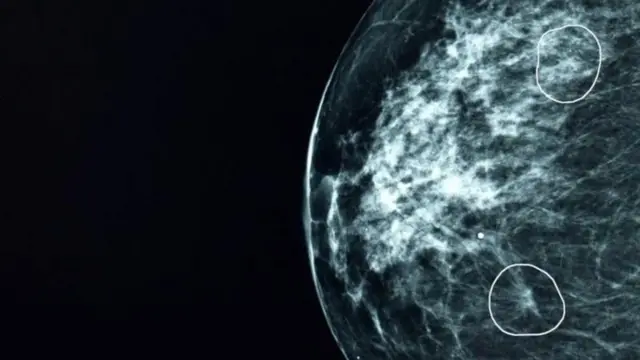

பிரிட்டிஷ் மருத்துவமனைகளில் பரிசோதிக்கப்பட்ட ஒரு செயற்கை நுண்ணறிவு (AI) கருவி, மருத்துவர்களால் கவனிக்கப்படாமல் போன 11 பெண்களில் மார்பக புற்றுநோயின் சிறிய அறிகுறிகளை அடையாளம் கண்டுள்ளது.

மியா(MIA) என்று அழைக்கப்படும் இந்தக் கருவி, பிரிட்டனில் உள்ள பல சுகாதார மையங்களில் சோதிக்கப்பட்டது. இந்த கருவி கிட்டத்தட்ட 10,000 மேமோகிராம்களை பகுப்பாய்வு செய்தது.

அவற்றில் பெரும்பாலானவை புற்றுநோயின் அறிகுறிகளைக் காட்டவில்லை. ஆனால் மருத்துவர்களால் கண்டறியப்படாத 11 நோயாளிகளை அந்தக் கருவியால் வெற்றிகரமாக அடையாளம் காண முடிந்ததுள்ளது.

ஆரம்ப கட்டங்களில், புற்றுநோய்கள் மிகவும் சிறியதாகவும், அடையாளம் காண்பது கடினமாகவும் இருக்கும்.

மனிதக் கண்ணுக்கு தெரியாத அத்தகைய கட்டிகளை, செயற்கை தொழில்நுட்பக் கருவியால் சுட்டிக் காட்ட முடிந்தது.